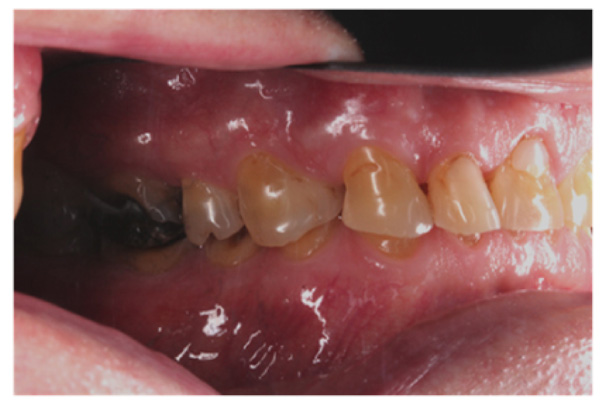

The patient presented with competent lips, an average lip line, normal TMJ function, and a mild Class II Division I incisor relationship with an increased overbite. The preoperative pan-oral radiograph is shown in Fig. (1). Boney exostoses and a large mandibular torus in the lower right mandible were present. The intra-oral presentation of the teeth is shown in Figs. (2-6). The patient had good oral hygiene and a healthy periodontium. The teeth had a glossy, smooth, and glazed appearance, showing cupping of the occlusal surfaces with significant loss of hard tissue and yellow color from the underlying dentine. This presentation was indicative of severe generalized tooth wear with exposed dentine in all sextants. The palatal, occlusal, and incisal surfaces were mainly affected, with lower buccal surfaces exhibiting more wear than the lower lingual, resulting in a reverse curve of Monson. The maximum BEWE score of 18 was recorded, meaning that the tooth with the most severe wear in each sextant had greater than 50% surface loss [9]. Several posterior teeth had amalgam restorations with defective margins (FDI 16, 26, 27, 37, and 47), as shown in Figs. (5 and 6). All teeth responded normally to pulp sensibility tests (cold test). The radiographs did not show any apical pathology to be present, but the pan-oral shows the scooped-out appearance of the lower molars.

IPS Empress Direct ® (Ivoclar Vivadent, Schaan, Liechtenstein) composite was syringed onto the worn surface and into the stent,which was seated onto the tooth. The composite was cured through the stent for 20 seconds; then the stent was removed, and the composite curing light was used again to ensure afull set for a further 40 seconds. The PTFE tape was removed, the excess composite at the gingival margin was trimmed back with narrow and ultra-fine diamond finishing burs, and a final polish was performed using Shofu Super-Snap Rainbow® discs (Kyoto 605-0983, Japan). The resultsare shown in Figs. (8-10). The slight increase in the vertical dimension is seen when comparing the pre-operative frontal image (Fig. 2) with the post-op image (Fig. 8), where some of the labial surfaces of the lower incisors is now visible, which was planned from the outset.